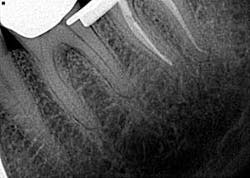

• File separation

Spin, spin, and snap! This is my least favorite endodontic complication (figure 3), which is why I wrote an entire article on it.